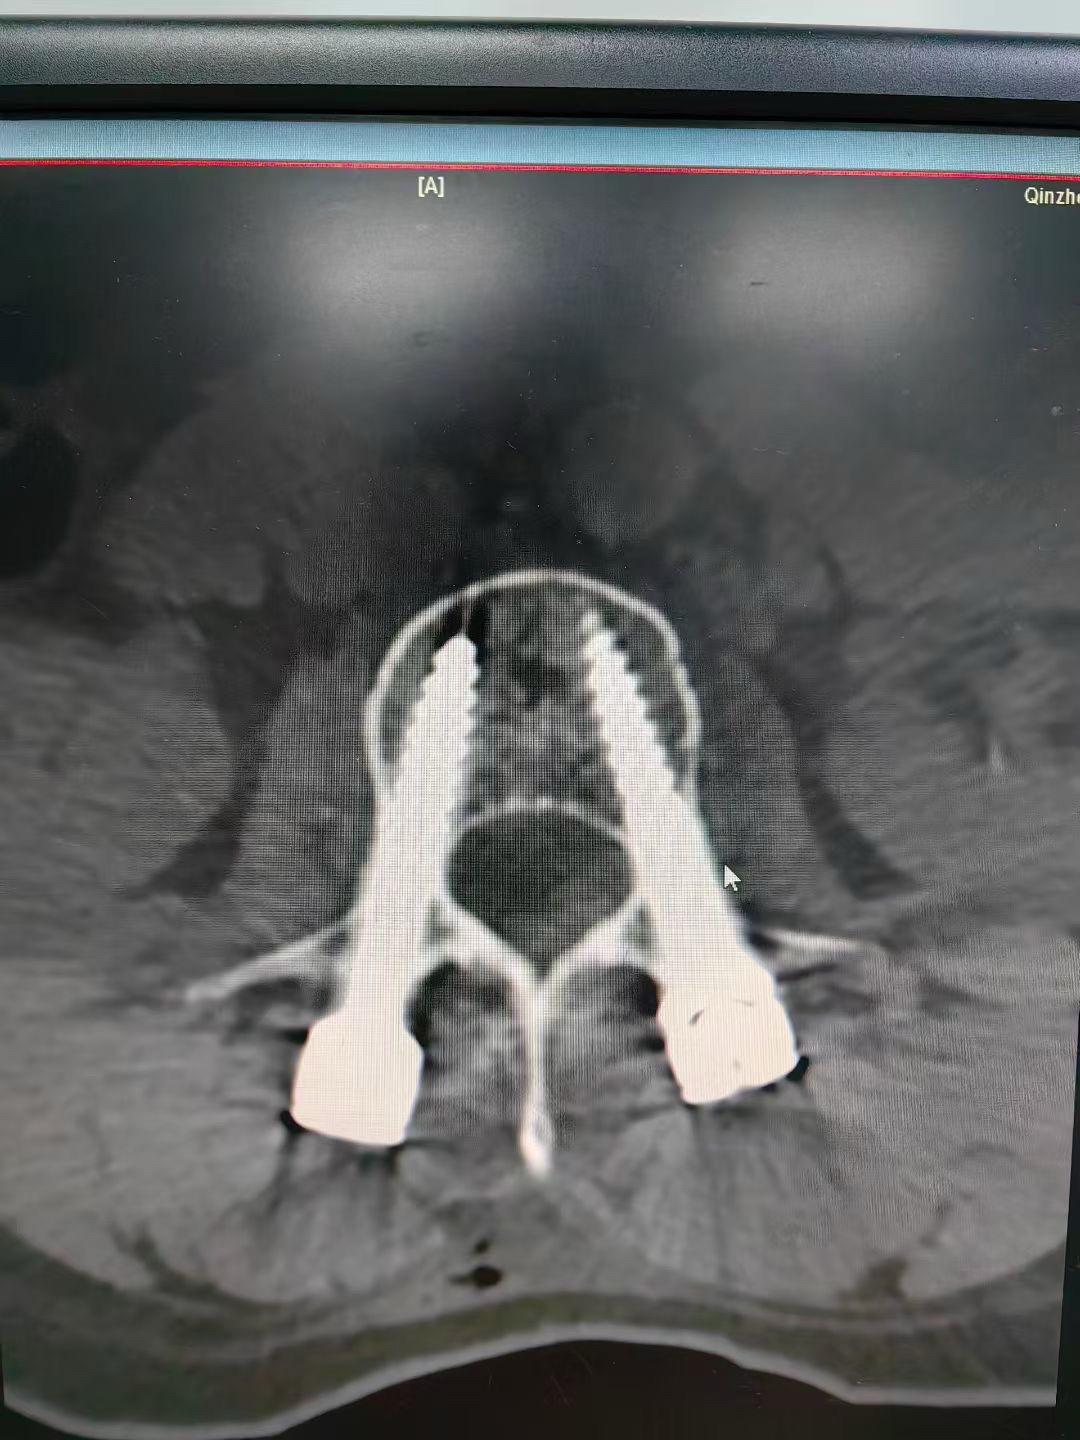

腰1爆裂性骨折,通过闭合复位也是能达到理想的

62岁外伤导致腰3爆裂性骨折,闭合复位,椎体复位稍差,但是椎管的复位还是满意